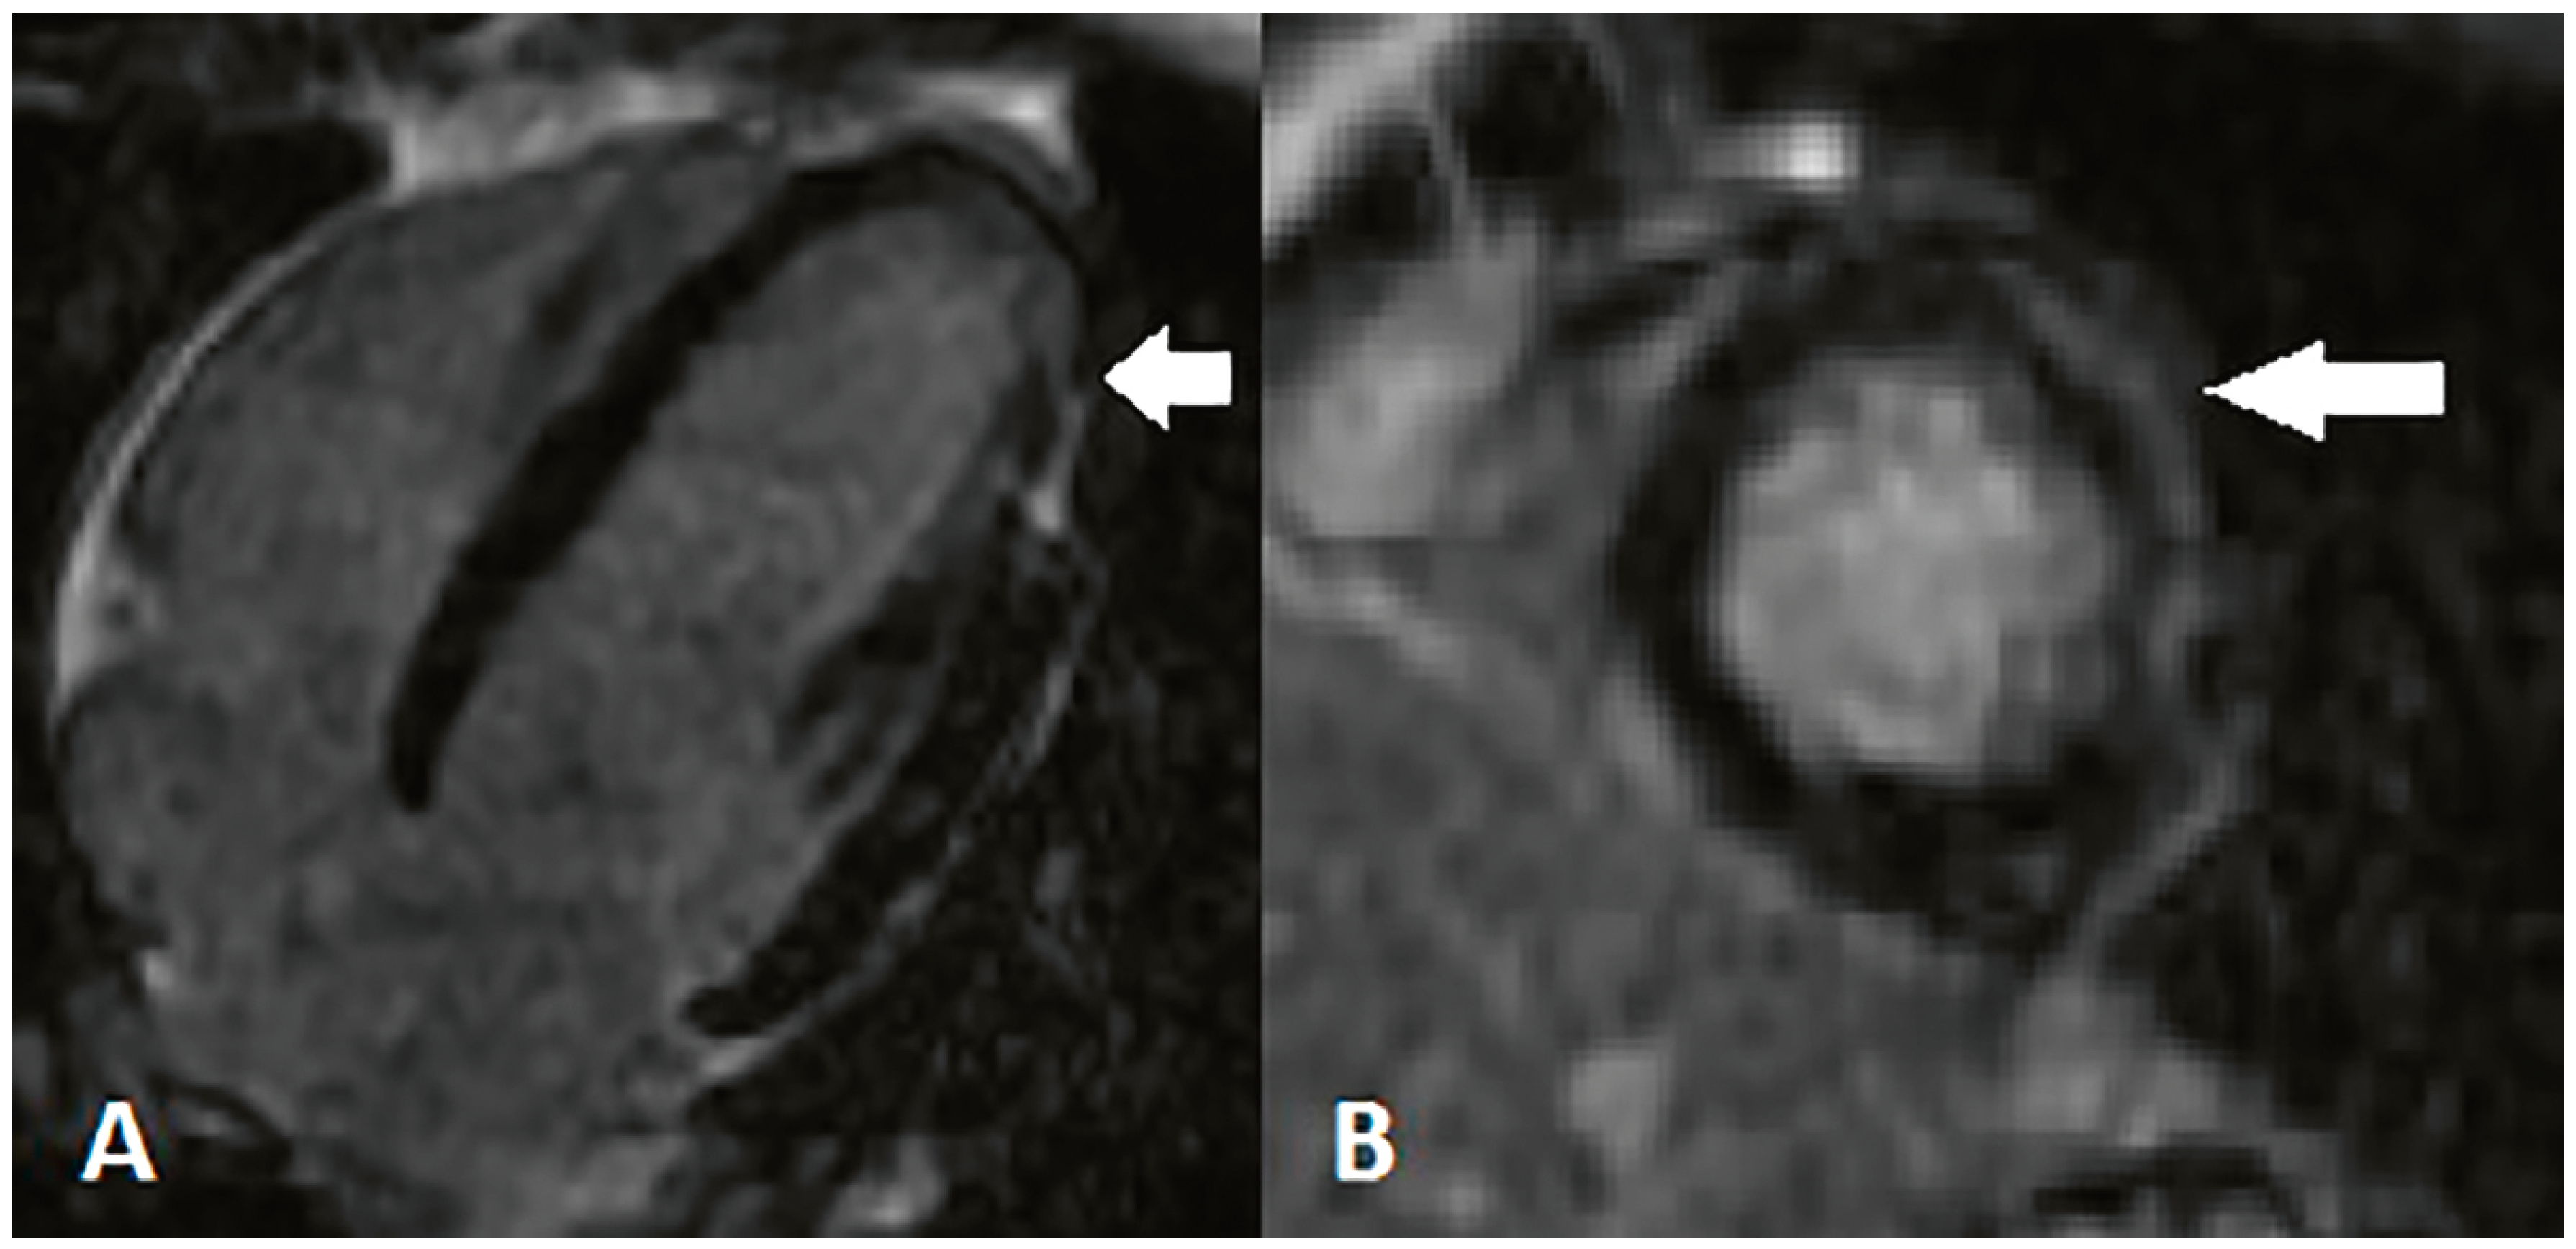

- Patient 1

- Patient 2

- Patient 3